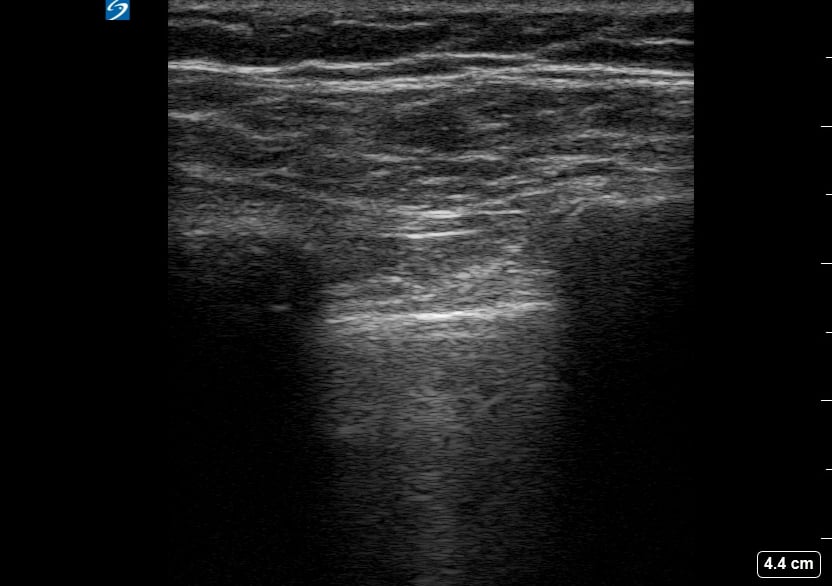

A pneumothorax, or collapsed lung, occurs when air leaks into the space between the lung and chest wall, causing the lung to partially or completely deflate. In a medical setting, prompt diagnosis is crucial to prevent respiratory distress. Ultrasound is a valuable tool for quick assessment, revealing characteristic signs like the absence of lung sliding or the presence of a “barcode” or “stratosphere” sign in M-mode, aiding rapid clinical decisions.

Ultrasound imaging for pneumothorax offers a non-invasive, real-time method for detection, especially in emergency and critical care. Key ultrasound findings guide clinicians in identifying this potentially life-threatening condition, facilitating timely intervention and improved patient outcomes. Understanding these signs is essential for medical professionals utilizing point-of-care ultrasound for lung pathology.